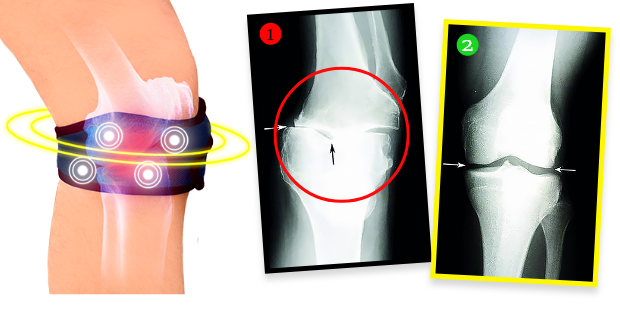

Gospa Helena je po tretmaju naredila rentgensko sliko in izkazalo se je, da so bile degenerativne spremembe v kolenu popolnoma odstranjene! Zdravnik je bil osupel – ni vedel, kaj naj reče. In dejstvo je, da se zaradi biomagnetnega traku Helenino stanje kolena ni samo nehalo slabšati. Hrustanec in občutljive strukture v sklepu so se regenerirale, kolenu pa se je vrnila funkcionalnost kot pred leti. Trak oddaja naravno in varno biomagnetno polje, ki prodira v najgloblja tkiva sklepa, hrani in obnavlja hrustanec, obnavlja njegovo elastičnost in odpornost ter spodbuja nastajanje sinovialne tekočine, ki med gibanjem blaži in ščiti pred bolečim trenjem. Gre za popolnoma neinvazivno in varno terapijo.